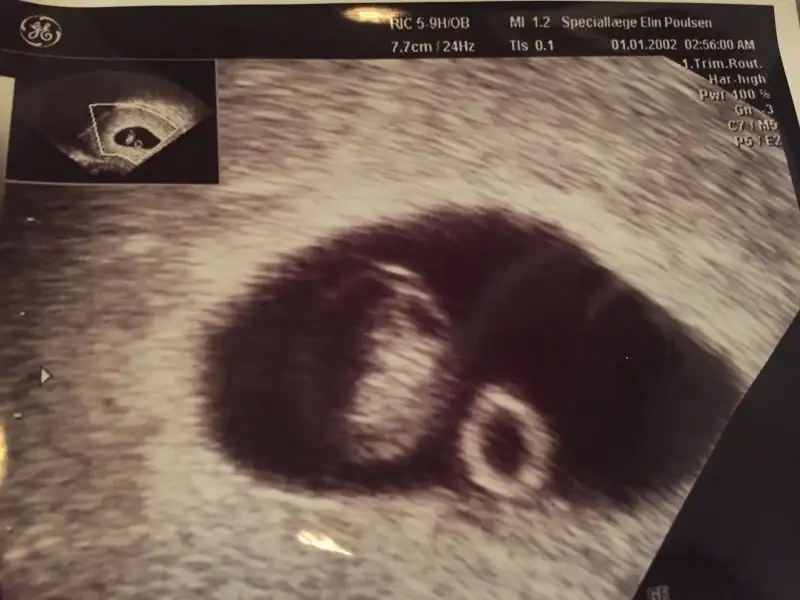

ayy saçmalamışım daha 5. haftanın içndeymişsin. ben senden 6 veya 7 haftalık ultrason görüntüsü istiyorum. dikkat etmemişim. zamanı gelince bana yollarsın tahminde bulunuruz :)Sana hangi cinsiyeti gösteriyor pikolata ?

istersen bebeğin kesedeki konumuna göre tahmin bölümüne 6 ya da 7 haftalık ultrason fotosu at. bir de ramzi teorsine öre tahminde bulunalım. sen de benim gibi cinsiyetini çok merak ediyorsun :)